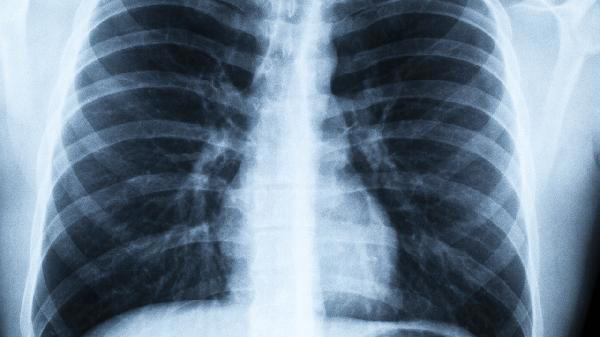

肺气肿患者常常陷入两难境地:既需要适当运动改善肺功能,又担心活动会加重气喘。其实选对方法,日常活动也能成为天然“康复训练”。掌握这几个小技巧,连晾衣服都能变成呼吸锻炼。